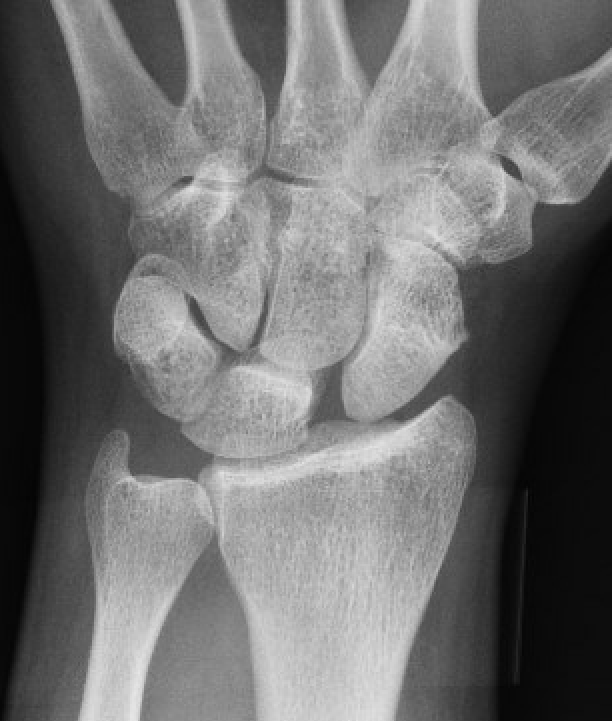

X-ray

Scapholunate gap > 3 mm

AP

| Terry Thomas sign | Cortical ring sign | Scaphoid shortened |

|---|---|---|

|

Increased scapholunate interval > 3 mm compared with other side |

End on view of distal scaphoid due to flexion | Shortened due to flexion |